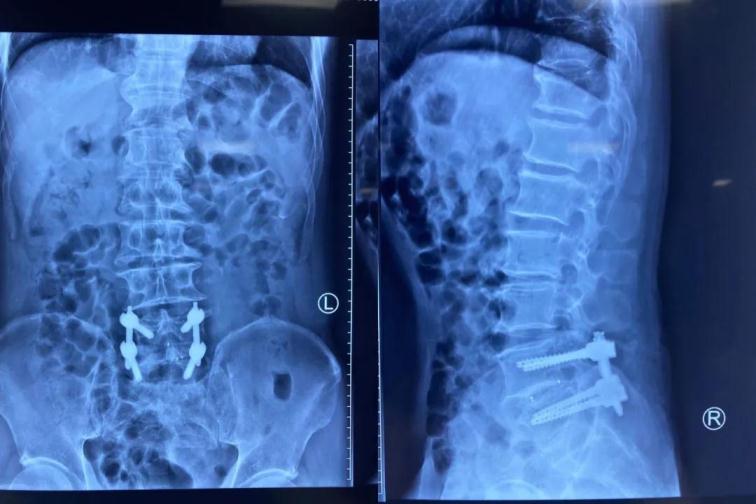

術(shù)后復(fù)查